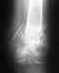

Выполнили открытую репозицию (остеосинтез - 2 пластины 14 винтов). В послеоперационный период наступил на ногу (был в лангете с эластичным бинтом).Три недели назад удалили металлоконструкции.При нагрузке на ногу и ходьбе и особенно отталкивании носком болит ахилово сухожилие и связки/сухожилия во "впадинах" по сторонам от него. Но носок встать совсем не могу.При визуальном осмотре можно отметить, что голень смещена к пятке (в сравнении со здоровой ногой).http://dl.dropbox.com/u/58743910/Published/mamitko%20ankle.zipТут снимки через два месяца после операции и свежие, без металлоконструкций.Возможно ли исправить сустав?В тайне еще надеюсь заниматься спортом.